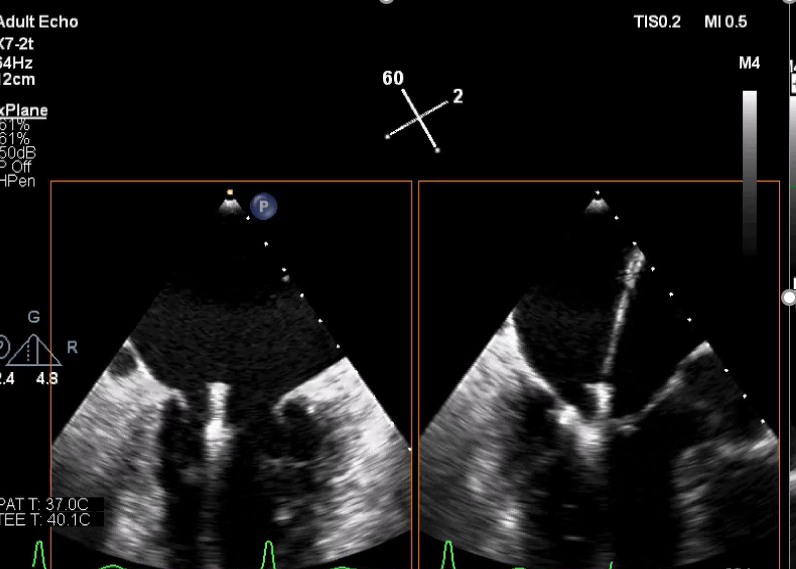

3D视图打开夹子

3D视图下观察二尖瓣双孔形态

3D-color:残余少量返流